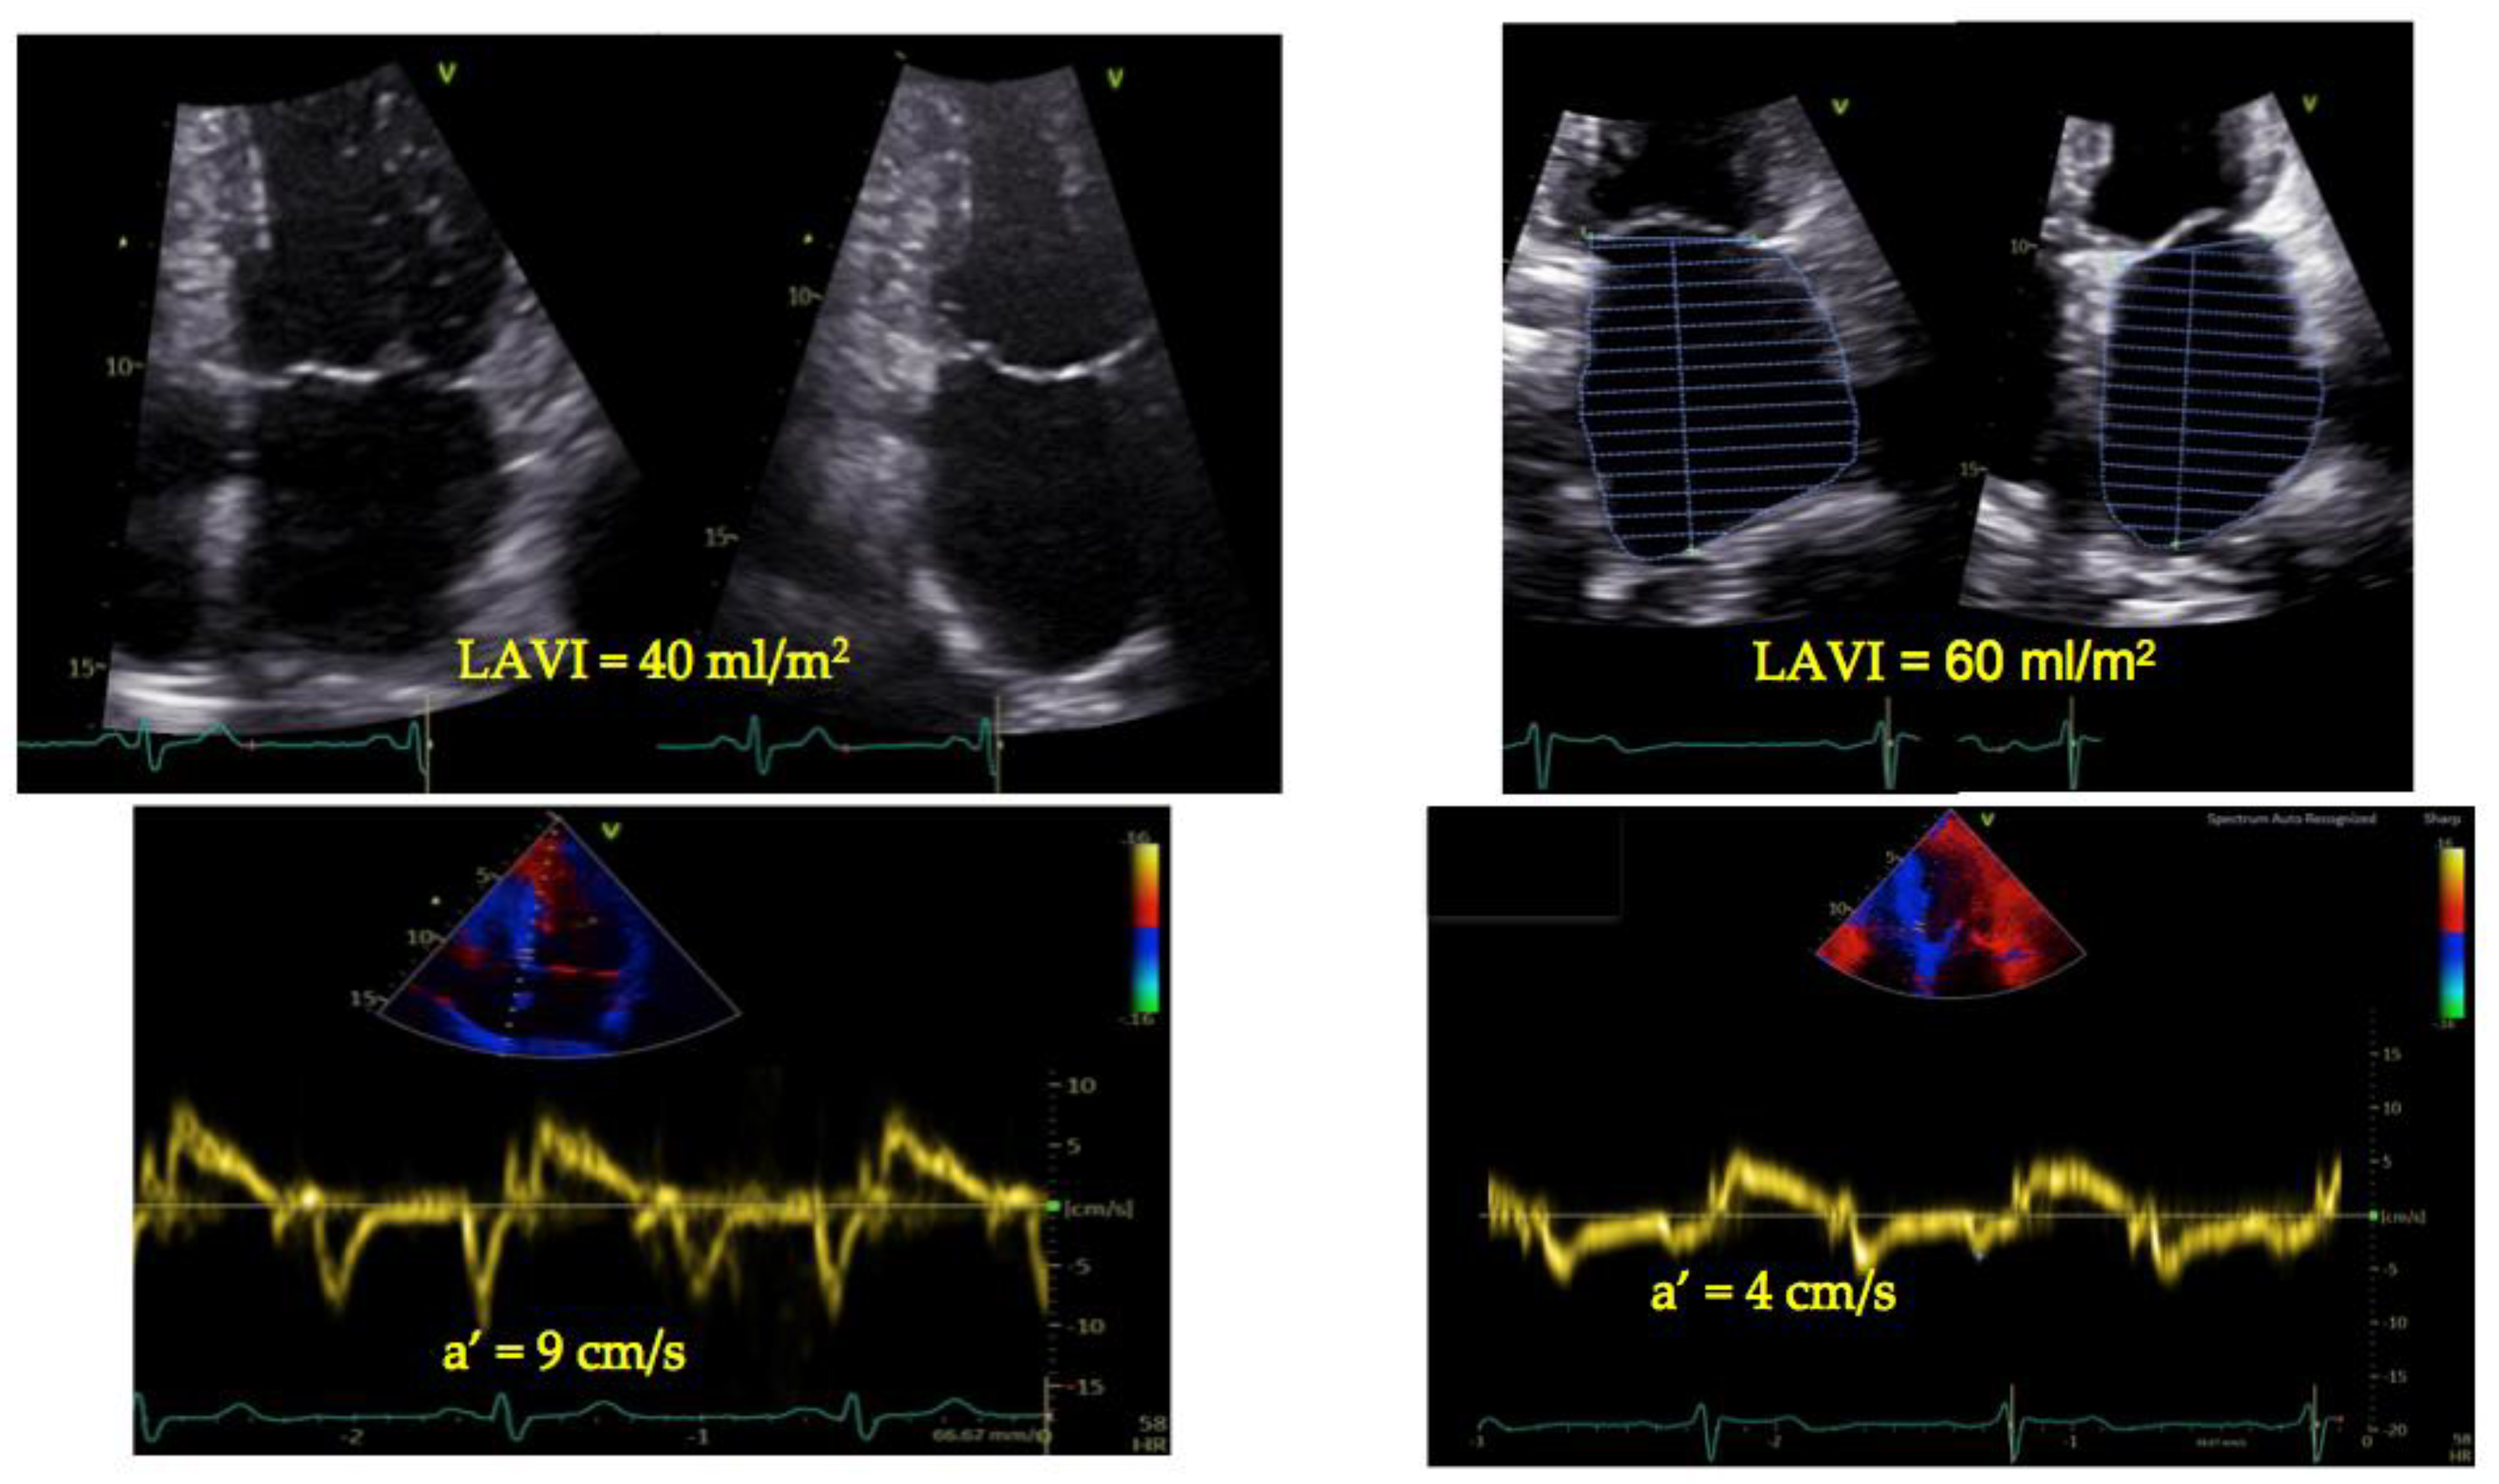

6. TDI-a’ and Outcome

7. TDI-a’ Integrated Echocardiographic Indices

| Studies with LAVI/a’ (LACI) | ||||

| Stahrenberg et al., 2011 [128] | Cerebral ischemia | Prospective | LAVI/a’ < 2.5 to rule out AF | AF onset |

| Park et al., 2011 [134] | Patients with dyspnea (NYHA II-IV) | Prospective | LAVI/a’ ≥ 4 higher incidence of outcome | Cardiac death/ rehospitalization HF |

| Benfari et al., 2021 [137] | HFrEF in sinus rhythm with MR | Prospective | LAVI/a’ ≥ 6 excess mortality | Survival |

| Essayagh et al., 2022 [138] | Patients with floppy mitral valve in sinus rhythm | Prospective | LAVI/a’ ≥ 5 excess mortality | Survival |

| Benfari et al., 2023 [139] | General population | Prospective | LAVI/a’ > 3.9 | AF onset independently from CHARGE-AF and CHA2DS2-Vasc |